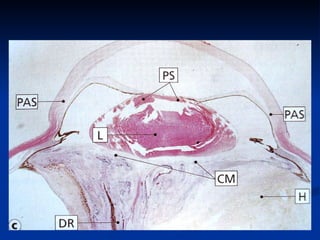

Difficult intra-op  Iris atrophy Sclerosis of pupillary sphincter Cyclitic membranes PS and PAS Anterior capsule sclerosis Iris haemorrhage Angle neovascularisation  Miotic pupil Synechiae Glaucoma